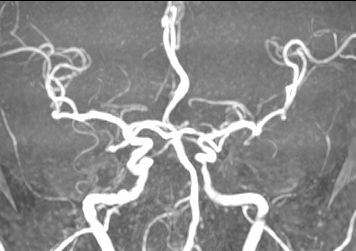

术后患者症状明显减轻,NIHSS评分2分。第二天复查MRA,血管保持通畅。

结合CTA结果,提示左侧颈内动脉起始部至颈内动脉末端未见显影,起始部成鼠尾征改变,前交通动脉开放,双侧大脑中动脉显影良好。MIStar图像提示核心梗死灶和缺血半暗带较小,但是MTT提示左侧大脑中动脉流域区明显延长。

4、将微导丝+微导管小心通过狭窄部位,至于LMCA M1段,手推造影剂示真腔,撤出微导丝,送入长交换导丝撤出微导管,沿微导管送入赛诺2.0×10mm-152.8cm球囊至狭窄处,7atm充盈球囊及回抽,造影见狭窄较前改善,残余狭窄10%,远端血流速度改善,观察10分钟后造影见远端血流无明显变化。